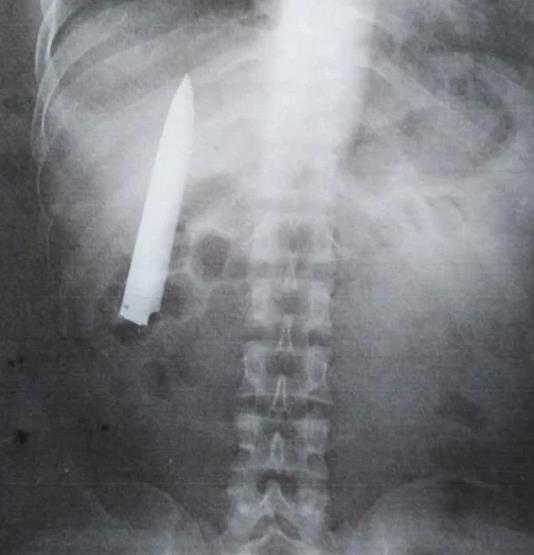

体检往往能查出很多人们察觉不到的问题,但有时候一些身体状况可能把医生也会吓一跳。近日,菲律宾一名男子因为天冷胸口就会疼,趁着入职体检就拍了一个X光片,结果让医患双方都惊讶不已:男子右胸内竟然藏着一把10厘米的长刀。

据每日邮报3月25日报道,现年36岁的男子肯特一年多来只要天气变冷,他的胸口就会疼痛不已。最近他准备应聘一家矿场的矿工职务,所以按照要求就到医院体检,顺便拍个X光看看胸口有无问题。